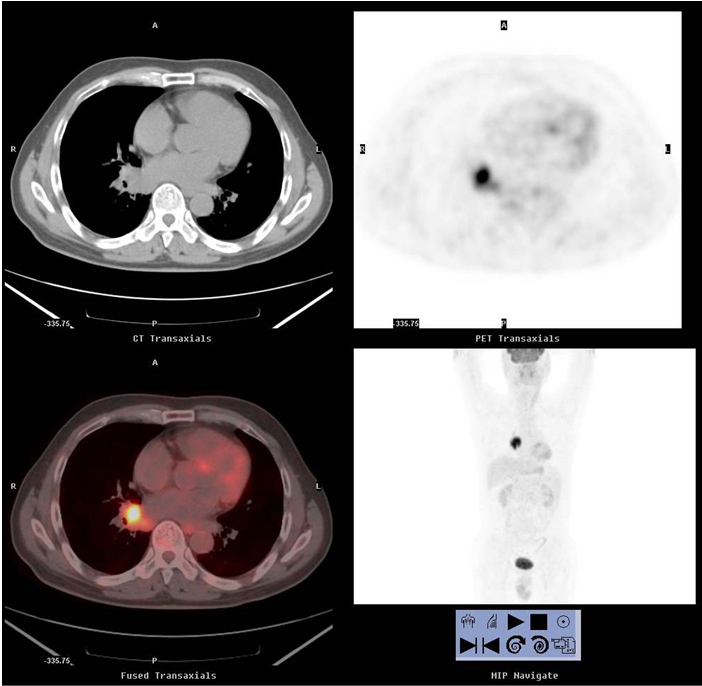

患者,男性,78歲,臨床診斷為左肺癌。臨床擬行放療。 CT示左肺占位伴肺不張,腫瘤邊界不清。PET清晰顯示腫瘤邊界,為放療靶區(qū)勾畫提供準(zhǔn)確依據(jù)。